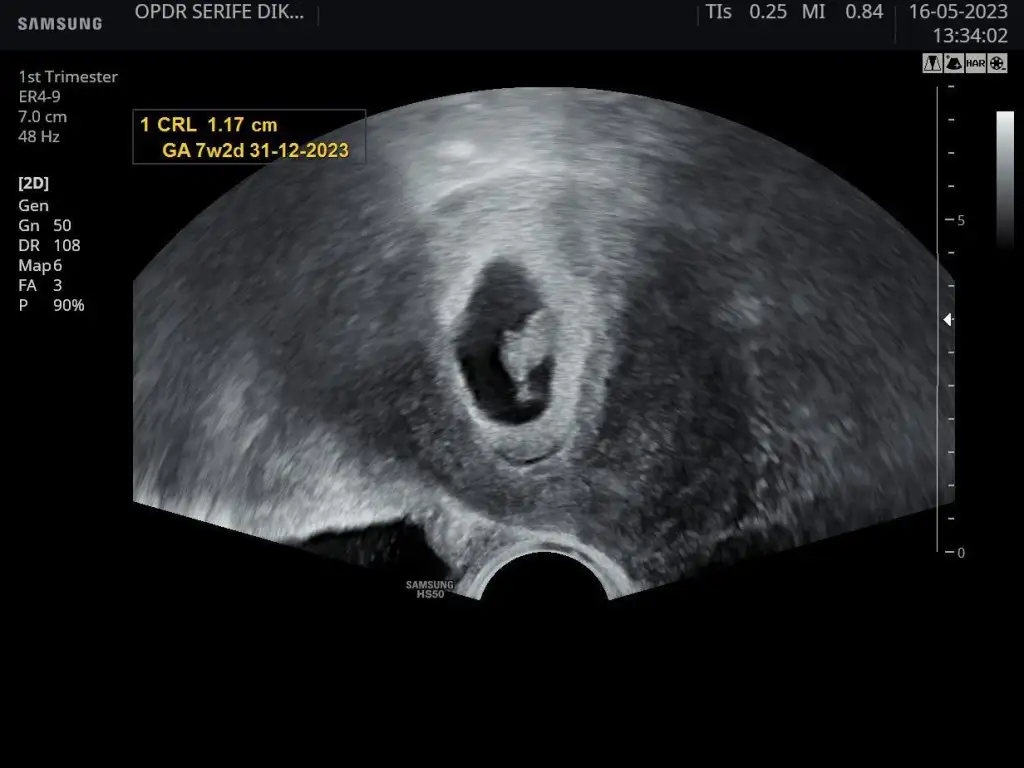

Tam 9 haftalık olmuşuz.

Kalp atımı 156 dedi.

Hareketli dedi

Haftasıyla uyumlu dedi. Tam adet bitimi hamile kalmışsın dedi.